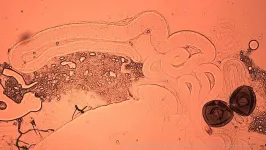

The researchers carried out a meta-analysis of 115 human studies (involving 54,889 men) and 56 studies across 30 non-human species. This confirmed that mature sperm in storage generally deteriorates in quality independently of the age of the male – a process called post-meiotic sperm senescence.

In humans, longer periods of sexual abstinence were associated with increased sperm DNA damage and oxidative stress, along with reduced sperm motility and viability.

Co-lead author Dr Rebecca Dean (Department of Biology, University of Oxford) said: "Because sperm are highly mobile and have minimal cytoplasm, they quickly exhaust their stored energy reserves and have limited capacity for repair. This makes storage particularly damaging compared to other types of cells. Our study highlights how regular ejaculation can provide a small but meaningful boost to male fertility."